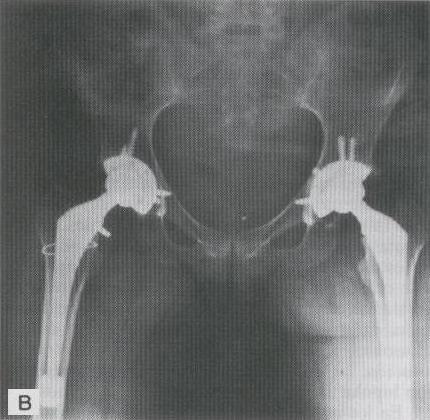

COLOCACION DE UNA PROTESIS HIBRIDA EN PACIENTE DE MEDIANA EDAD